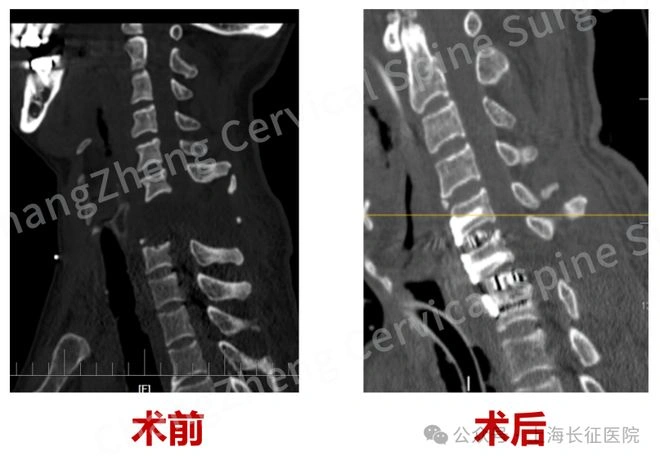

术前与术后影像的鲜明对比,仿佛是时间的见证者,清晰地展现了手术的显著成效。陈华江教授满怀信心地展望未来:“我们怀揣着对医学的敬畏与热爱,将继续深耕于颈椎外科这片充满挑战的领域,不断克服重重困难,突破技术难关,为那些徘徊在生死边缘的患者,点亮希望的灯塔,带来新的生机。”